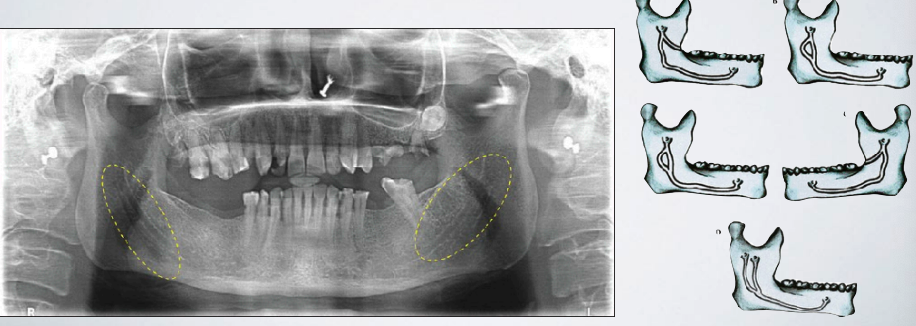

what are some anatomical reasons an inferior alveolar nerve block might fail?

Bifid inferior alveolar nerve/canal (A second mandibular foramen may exist)

if a patient has a bifid inferior alveolar nerve/canal, the nerve block might fail. how can you correct this?

second injection inferior to the normal anatomical landmark